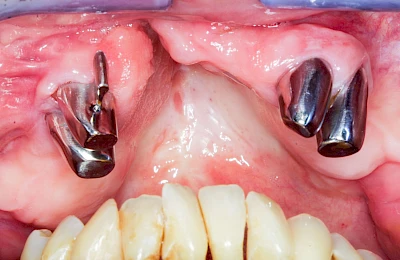

Überbein (Exostose)

Überbeine im Bereich der Kiefer sind gar nicht so selten. Häufiger im Bereich der Seitenzähne unterhalb des Zahnfleisches, aber auch in der Mitte vom Gaumen. Überbeine haben in dem Sinne keinen Krankheitswert, müssen also nicht operativ entfernt werden, wenn diese nicht stören. Überbeine können ein Anzeichen für Knirschen und Pressen sein.